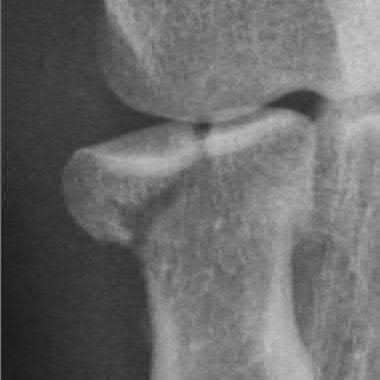

A 25-year-old woman sustains a fall on an outstretched hand. She complains of elbow pain. Examination reveals tenderness over the lateral elbow and pain on elbow motion. Injury radiographs and CT scans are shown in Figures A and B, respectively. What is the next best step?

This patient has Mason II radial head fracture. ORIF will give the best results.

Non-/minimally displaced radial head fractures without a block to rotation can be managed nonoperatively. Complete articular fractures with >=3 fragments do better with radial head replacement. Indications for ORIF include large articular surface fragments, > 2 mm of displacement, mechanical block to forearm rotation, or associated fractures or ligament injuries requiring surgery.

Pike et al. retrospectively compared patients undergoing ORIF for isolated radial head fractures with radial fractures associated with other fractures/dislocations. They found no differences in pain/disability and complications or secondary capsular release between groups.

Yoon et al. retrospectively compared isolated partial articular displaced (2-5mm) radial head fractures treated nonoperatively vs ORIF. They found no clinical benefit with ORIF compared to non-operative management. The ORIF

group had more complications. Younger patient age and larger fracture displacement favored operative intervention. Younger patients fared worse.

Figures A and B are radiographs and 3D reformatted CT images showing a displaced partial articular radial head fracture.

Incorrect Answers:

Answer 1: Nonoperative management is indicated for non-/minimally displaced fractures.

Answer 2: Excision is an option for small partial articular fragments = 3 fragments.